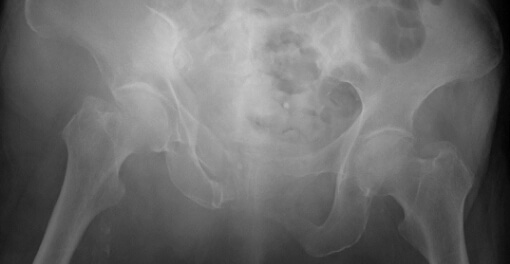

脆弱性骨盤骨折症例

転倒にて受傷した高齢女性。骨折部の転位が大きく疼痛も強かったため手術を行いました。手術は全身への負担が少ない低侵襲手術(小切開によるスクリュー固定)を行い、術後はすぐに荷重歩行訓練を開始しました。